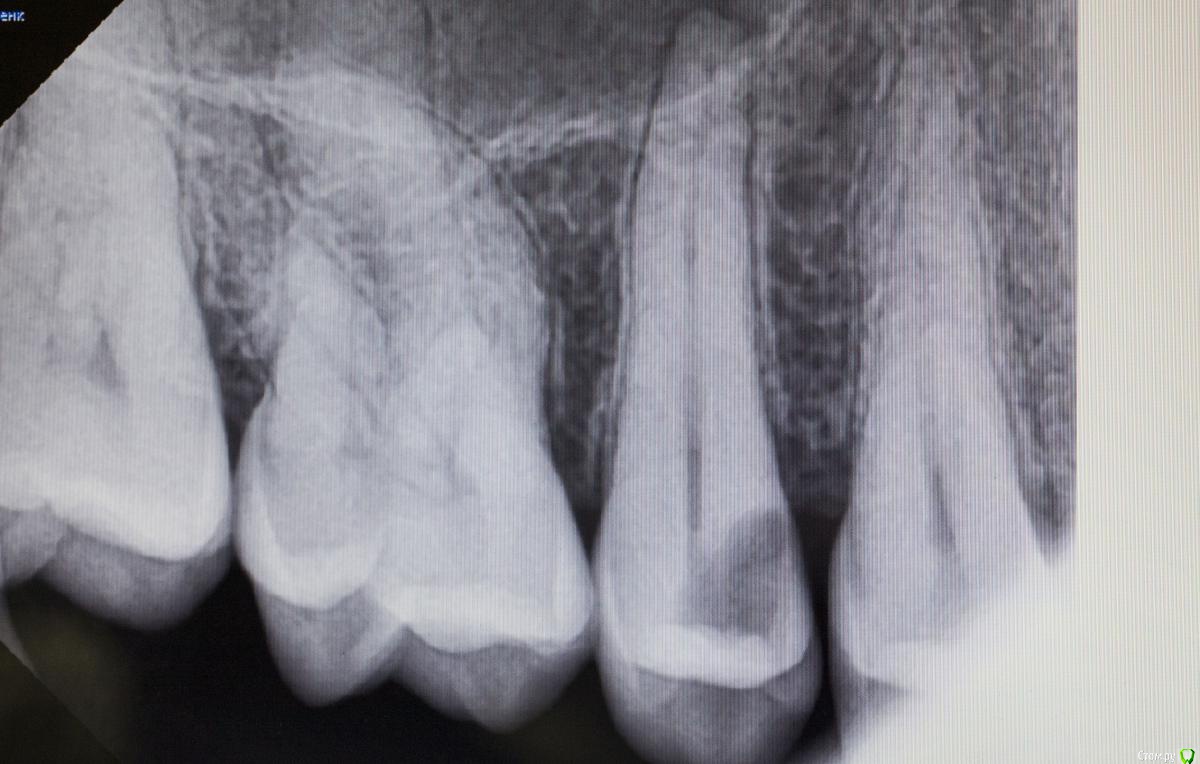

Kolchanov Опубликовано 19 апреля, 2018 Поделиться Опубликовано 19 апреля, 2018 Каплан, а есть какой-нибудь кейс с реальным поддесневиком. Где матрицу по полчаса вкорячиваешь. А то я все понимаю, эргономика, туда-сюда, но меня не покидает ощущение, что, когда попадается реально сложный случай, то микроскоп со вздохом отодвигается и начинается реальная жизнь стоматолога 7 Ссылка на комментарий

Kolchanov Опубликовано 19 апреля, 2018 Поделиться Опубликовано 19 апреля, 2018 Тут на фейсбуке какой-то доктор, кажется из лекторов, показывает случай с "поддесневым" разрушением, как он его назвал. И говорит, что чтобы не изменять профиль матрицы надо тефлоном подоткнуть вместо клина. А я смотрю и глаза протираю. Не вижу поддесневика. Коффер инвертирован, все путем. Ну, надо видеть конечно. Но я к чему, неужели только у меня что ни день то кариес-поддесневик? Ссылка на комментарий

Паращук Роман Опубликовано 20 апреля, 2018 Поделиться Опубликовано 20 апреля, 2018 Поддесневиков каждая третья полость. Далее или удлиняем и с помощью молотка и чей-то матери тулим матрицу,или удаляем. Ссылка на комментарий

Л Ю С Я Опубликовано 20 апреля, 2018 Поделиться Опубликовано 20 апреля, 2018 Матрицу тоже можно глубоко засунуть, не проблема, поджать фумкой, клином. Но контакта плотного получить, вот это реальная проблема 1 Ссылка на комментарий